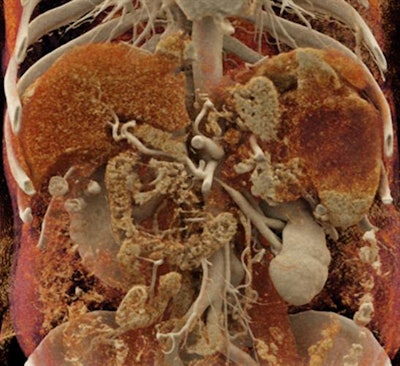

In the current article, the group discussed three distinct ways in which cinematic rendering could facilitate the evaluation of a variety of conditions affecting the spleen, including the following:

- Neoplastic processes: The intrinsic ability of cinematic rendering to accentuate texture enables it to reveal spleen lymphomas, the organ's most common malignancy, more readily than standard CT -- thereby facilitating cancer diagnosis and prognosis, the authors noted. For rare tumors such as littoral cell angiomas, cinematic rendering can pinpoint underlying abnormalities that may help physicians distinguish between benign and malignant cases.

- Accessory spleen: Accessory splenic tissue seen on CT scans is occasionally mistaken for a tumor, especially for cancer patients. Standard CT and volume-rendered CT scans are often inadequate for determining tissue type in these cases and require a follow-up nuclear medicine exam to make a definitive diagnosis.

But cinematic rendering may obviate the need for additional testing in such cases because of the high level of soft-tissue detail it provides, as well as the pronounced differences it shows between the texture of tumor and normal tissue, according to the authors. "There may be tremendous opportunity to utilize this methodology to improve lesion characterization by visualization of texture within tumors and accessory splenic tissue," they wrote.